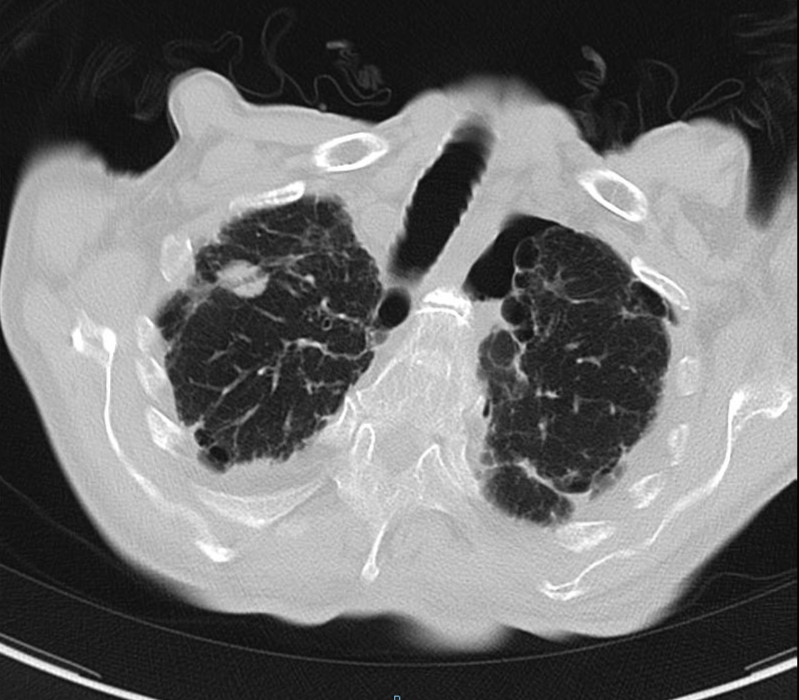

2020-01-08查胸部CT:双肺间质纤维化伴双肺气肿,双肺炎症,伴支气管扩张,右肺上叶结节样影,性质待定,双侧胸腔积液,纵膈多发肿大淋巴结,主动脉及冠状动脉硬化。

2020-08-31复查胸部CT:右肺结节影,结合病史考虑转移性病变,左侧局限性气胸,双肺气肿,双肺间质性病变,双侧胸腔积液;心脏增大,主动脉硬化。